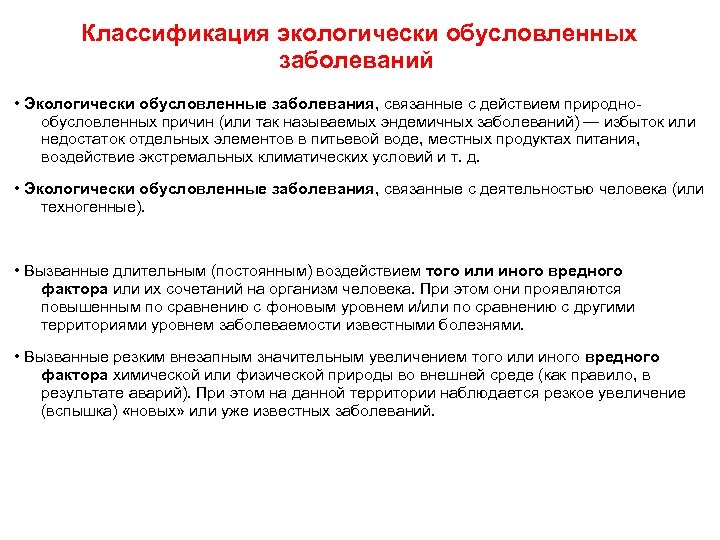

Классификация экологически обусловленных заболеваний • Экологически обусловленные заболевания, связанные с действием природно обусловленных причин (или так называемых эндемичных заболеваний) — избыток или недостаток отдельных элементов в питьевой воде, местных продуктах питания, воздействие экстремальных климатических условий и т. д. • Экологически обусловленные заболевания, связанные с деятельностью человека (или техногенные). • Вызванные длительным (постоянным) воздействием того или иного вредного фактора или их сочетаний на организм человека. При этом они проявляются повышенным по сравнению с фоновым уровнем и/или по сравнению с другими территориями уровнем заболеваемости известными болезнями. • Вызванные резким внезапным значительным увеличением того или иного вредного фактора химической или физической природы во внешней среде (как правило, в результате аварий). При этом на данной территории наблюдается резкое увеличение (вспышка) «новых» или уже известных заболеваний.

Классификация экологически обусловленных заболеваний • Экологически обусловленные заболевания, связанные с действием природно обусловленных причин (или так называемых эндемичных заболеваний) — избыток или недостаток отдельных элементов в питьевой воде, местных продуктах питания, воздействие экстремальных климатических условий и т. д. • Экологически обусловленные заболевания, связанные с деятельностью человека (или техногенные). • Вызванные длительным (постоянным) воздействием того или иного вредного фактора или их сочетаний на организм человека. При этом они проявляются повышенным по сравнению с фоновым уровнем и/или по сравнению с другими территориями уровнем заболеваемости известными болезнями. • Вызванные резким внезапным значительным увеличением того или иного вредного фактора химической или физической природы во внешней среде (как правило, в результате аварий). При этом на данной территории наблюдается резкое увеличение (вспышка) «новых» или уже известных заболеваний.